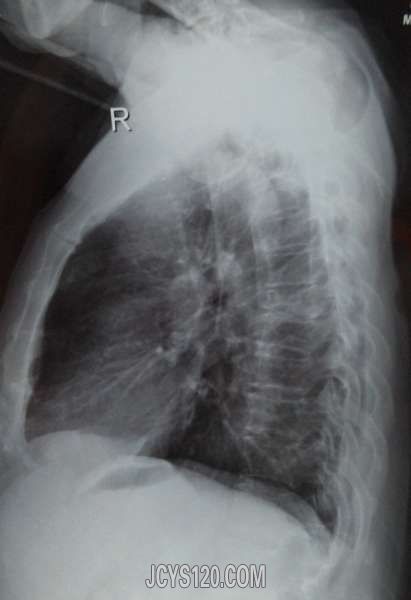

男,60岁,躯体活动受限。 我仅仅是上传了部分能够看清楚的X光片,大家先讨论 **** 本内容被作者隐藏 **** 阅读全文>